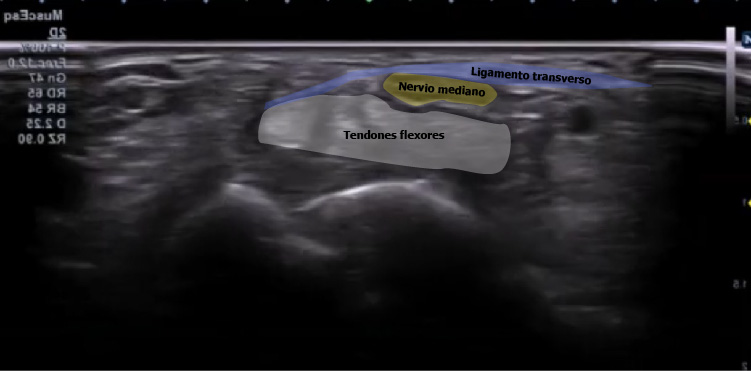

Esta imagen de un corte transversal de la muñeca, nos da un esquema muy claro sobre las estructuras que encontraremos.

De forma superficial al ligamento transverso del carpo, encontraremos el flexor cubital del carpo, el palmar largo (estos dos sin vaina sinovial) y el flexor radial del carpo. El palmar largo es un músculo inconstante, por lo que no siempre estará presente.

Si nos vamos a una capa más profunda, en lo que conocemos como el túnel del carpo, encontraremos una primera hilera de tendones que corresponden al músculo flexor superficial de los dedos.

La tercera capa en profundidad incluirá los cuatro tendones del flexor profundo de los dedos y el flexor largo del pulgar.

No hay que perder de vista que el nervio mediano se encuentra inmediatamente superior a los tendones de la musculatura flexora.

A la hora de explorar la región, realizaremos un corte transversal buscando el hueso pisiforme como nuestra referencia anatómica.

El nervio mediano discurre superficialmente a los tendones flexores superficial y profundo de los dedos. Tendrá una forma ovalada y en una interfase superior, veremos una película hiperecogénica que corresponde al ligamento transverso del carpo.